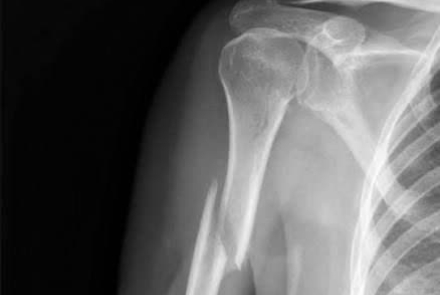

برای اولین بار در بیمارستان فاطمیه بادرود جراحی درمان شکستگی بازو با استفاده از پیچ و پلاک با موفقیت انجام شد.

این جراحی بزرگ و تخصصی و حساس توسط  پزشکان معالج جناب آقای دکتر حمیدرضا حاجی هاشمی، متخصص جراح ارتوپدی و سرکار خانم دکتر لیلی مهرزاد متخصص بیهوشی و مراقبت‌های ویژه انجام گرفت. جراحی فوق با همراهی و همکاری بی‌نقص کارکنان اتاق عمل انجام شد.